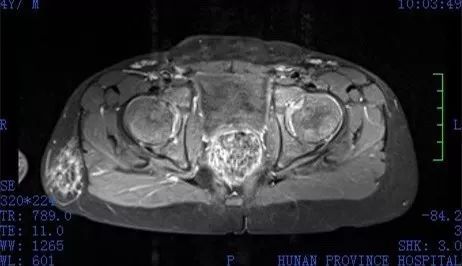

然而,兒子到了5歲時,卻因生殖器發育不良,只能蹲著上廁所,父母才感覺不對勁,趕緊帶著小孩就醫,經過詳細檢查後,醫師發現雖然男孩擁有正常男性的生殖系統,也沒有子宮、卵巢等女性生殖器,但他的染色體卻呈現「46XX」的女性染色體,因此才導致他的外生殖器發育較差。

▼男孩擁有正常男性的生殖系統。(圖/翻攝自《新浪網》)